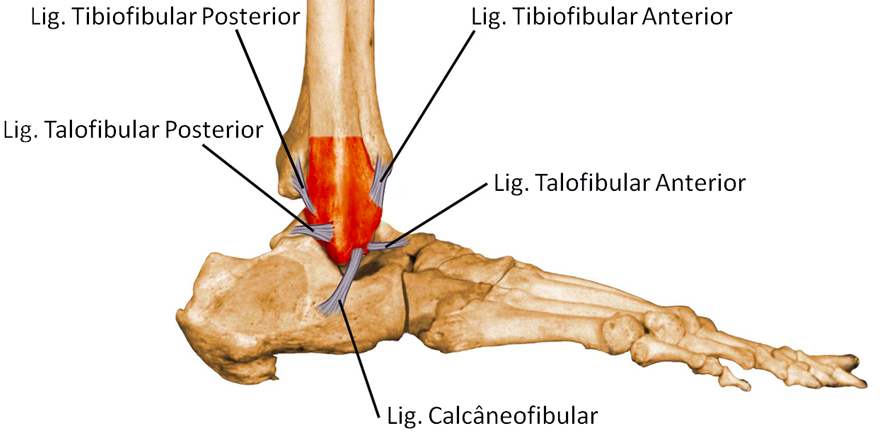

O complexo ligamentar lateral é formado por três ligamentos: o talofibular anterior (LTFA), o calcâneofibular (LCF) e o talofibular posterior (LTFP). Eles impedem que o pé exceda o movimento de inversão (para dentro) e a rotação interna. O ligamento talofibular anterior é o mais frágil e o que mais é lesionado nas entorses de tornozelo.

O ligamento da porção medial é chamado de deltóide. Possui duas camadas e impede a eversão (movimento para fora) e a rotação externa do pé. Esses ligamentos estão intimamente envolvidos com as fraturas do tornozelo e sofrem lesão e rupturas durante o trauma.